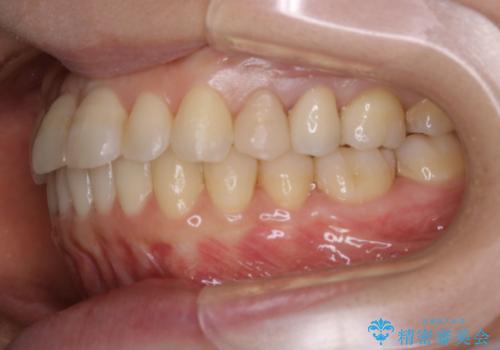

- 右上の2番目の歯が内側に入っているのと、下の前歯のがたつきが気になるとご相談にいらした方です。

上下左右の歯を後ろに動かして歯を並べるスペースを確保し、内側に入っていた歯を綺麗に並べ、前歯の中心もお顔の中心に合うようにしました。

矯正用アンカースクリューを埋入し、上下左右の歯を後ろに動かすことで歯を並べるスペースを作りました。

元々内側に倒れていた右下の奥歯は、ゴムかけを追加で行っていただくことによりしっかり起こすことが出来ました。